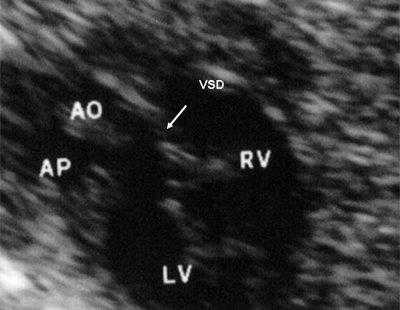

В равной степени это относится к дефекту межжелудочковой перегородки (рис. 6), простой форме транспозиции магистральных сосудов (рис. 7, 8), транспозиции магистральных сосудов с дефектом межжелудочковой перегородки (синдром Тауссиг - Бинга) (рис. 9), общему желудочку (рис. 10), общему артериальному стволу (рис. 10), двойному отхождению сосудов от одного из желудочков сердца (рис. 11).

Рис. 6. Дефект межжелудочковой перегородки. Длинная ось сердца. Стрелками показан дефект межжелудочковой перегородки.

LV и RV - левый и правый желудочек, АР - легочная артерия, АО - аорта, VSD - дефект межжелудочковой перегородки.